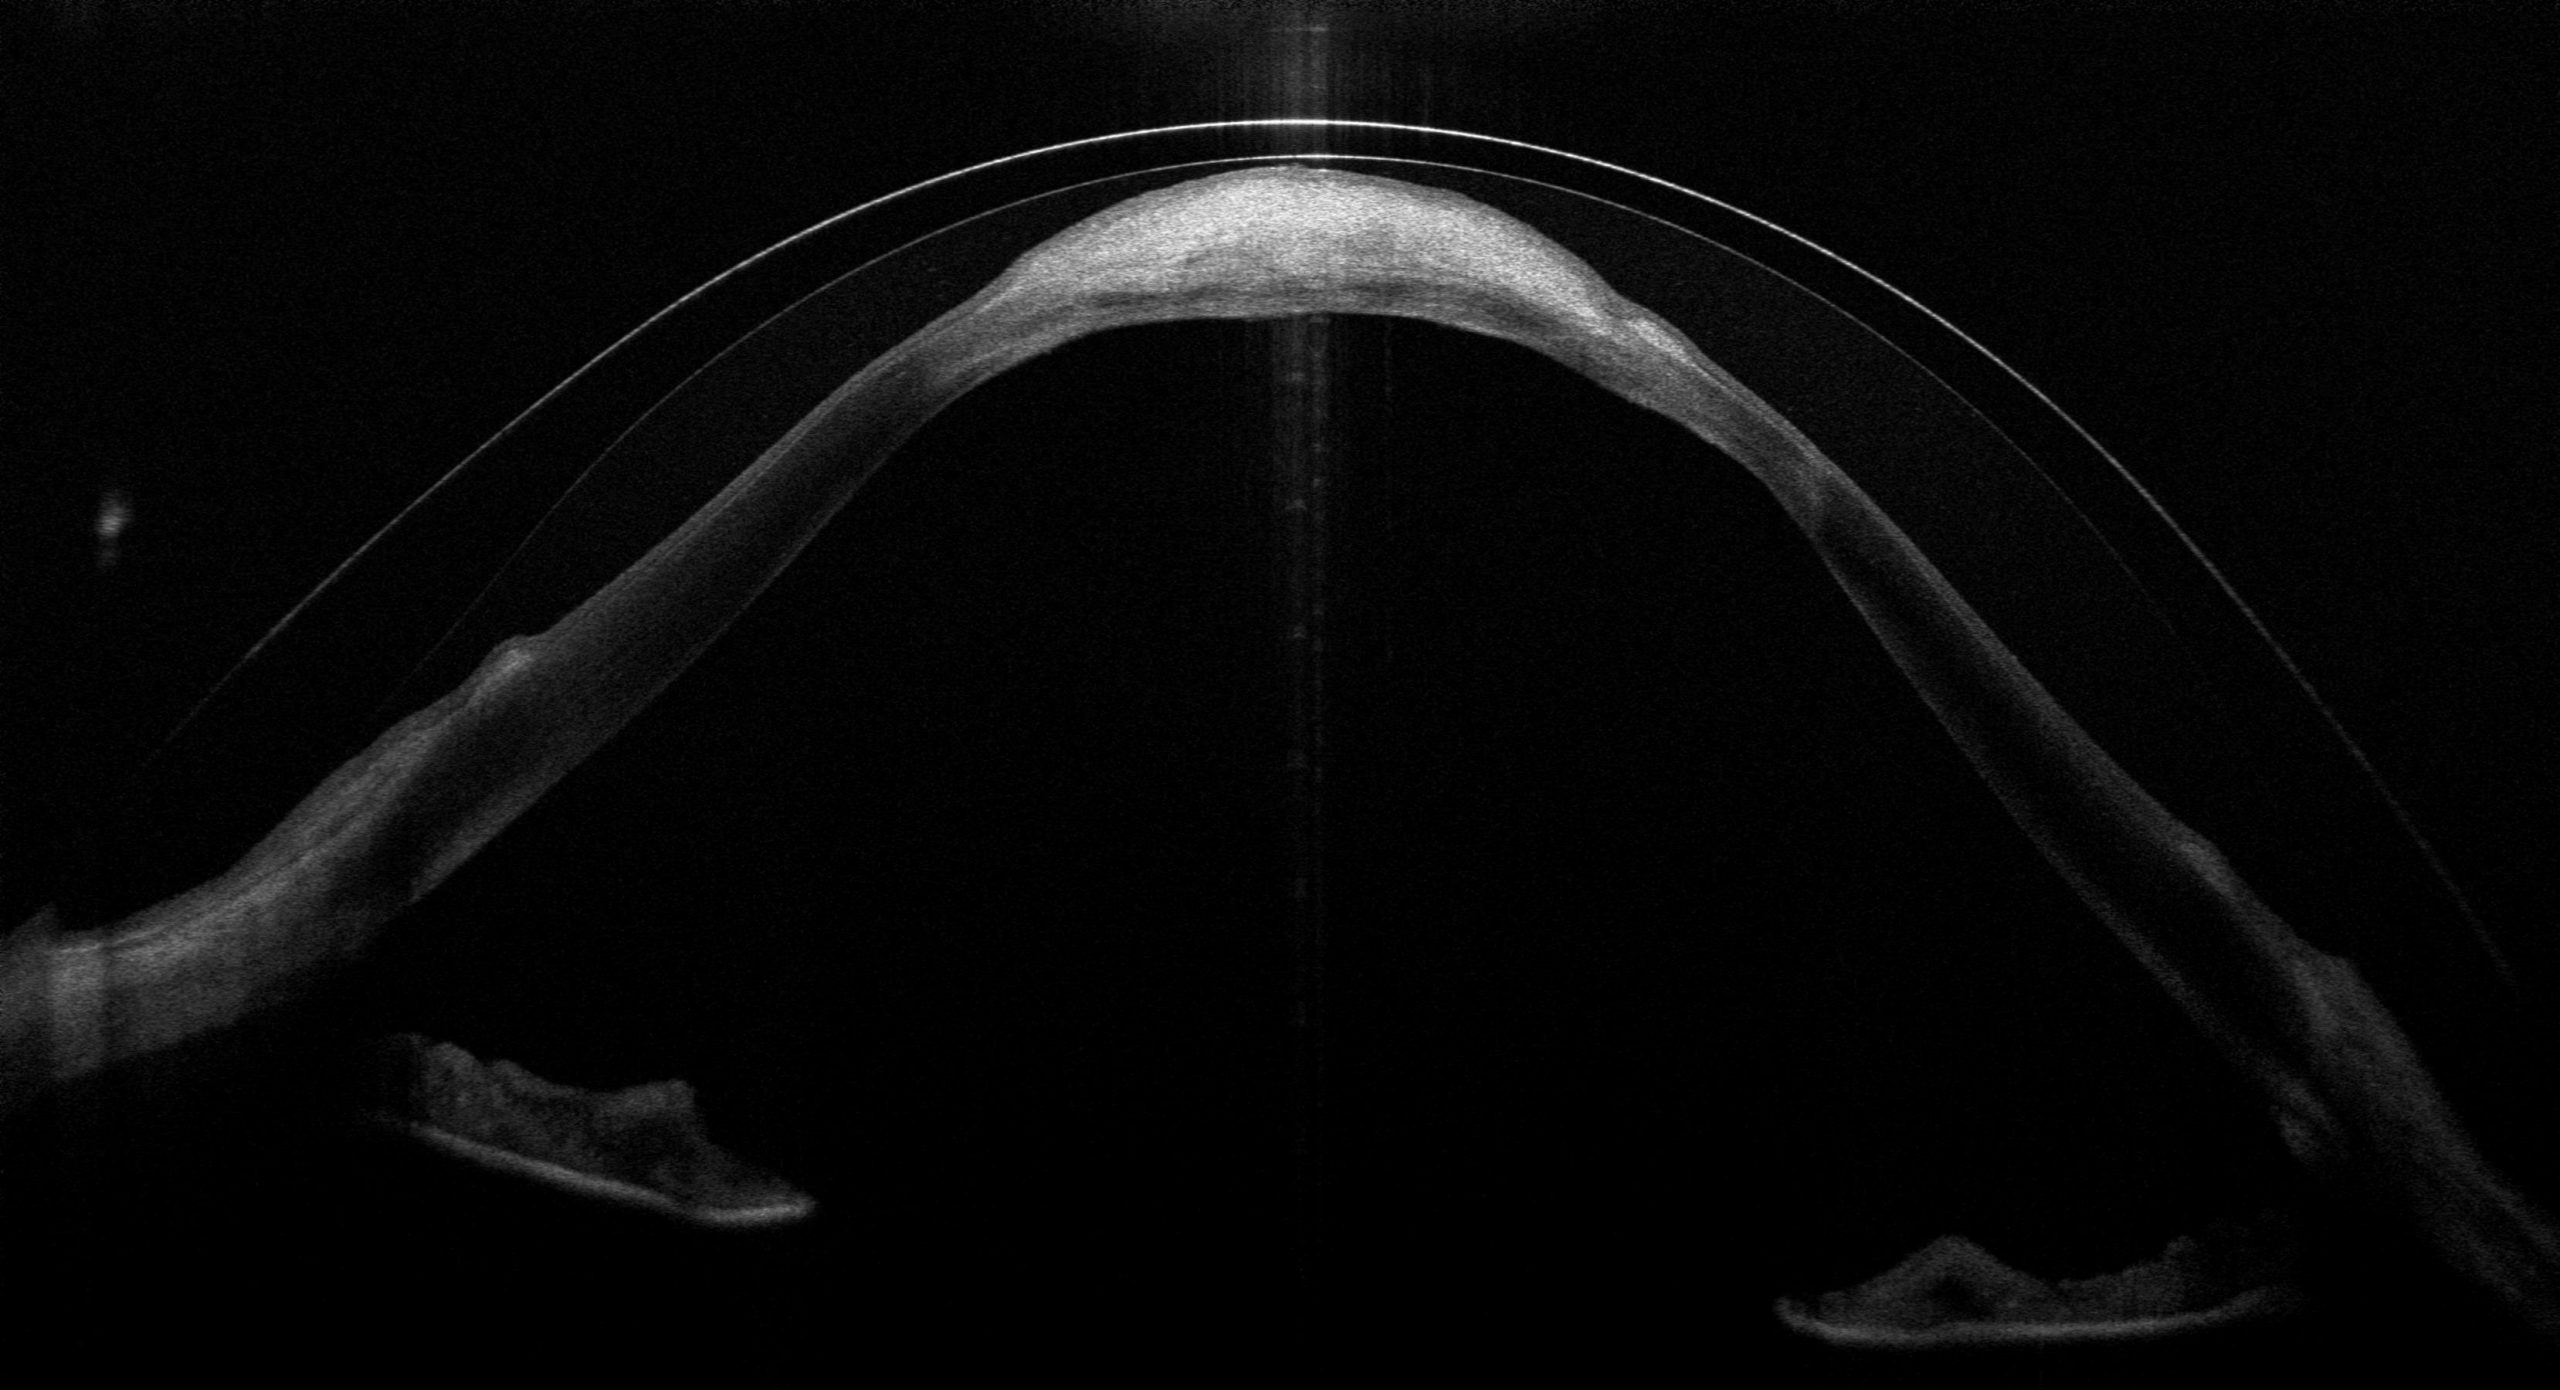

Die Optische Kohärenztomographie (OCT) ist eines meiner wichtigsten Werkzeuge bei der Anpassung und Kontrolle von Sklerallinsen – besonders bei komplexen Fällen wie diesem. Das OCT erstellt hochauflösende Querschnittbilder der Hornhaut und zeigt exakt, wie die Sklerallinse auf dem Auge sitzt: den Abstand zur Hornhaut, das Tränenreservoir darunter und ob irgendwo ein Kontakt entsteht. Was das OCT sichtbar macht, bleibt bei der Spaltlampenuntersuchung oft verborgen – denn ob die Linse tatsächlich auf der Narbe aufliegt, lässt sich mit bloßem Auge nicht beurteilen.

In den OCT-Aufnahmen dieses Falls wird genau das sichtbar: Der Querschnitt zeigt, wie die Sklerallinse sich bogenförmig über die Hornhaut wölbt – und wo sie im Bereich der Hydrops-Narbe aufliegt. Dieser Kontakt zwischen Linse und Narbengewebe wäre bei einer reinen Spaltlampenuntersuchung nicht erkennbar gewesen. Erst das OCT macht diese kritische Stelle sichtbar und ermöglicht eine gezielte Optimierung der Linsengeometrie.

Die aktuellste OCT-Aufnahme vom März 2026 zeigt eindrucksvoll die Auflage der Linse auf dem Narbenbereich – eine Information, die ausschließlich das OCT liefert. Gerade bei einem so ausgeprägten Hydrops sind regelmäßige OCT-Kontrollen unverzichtbar, um den Sitz der Linse langfristig zu beurteilen.